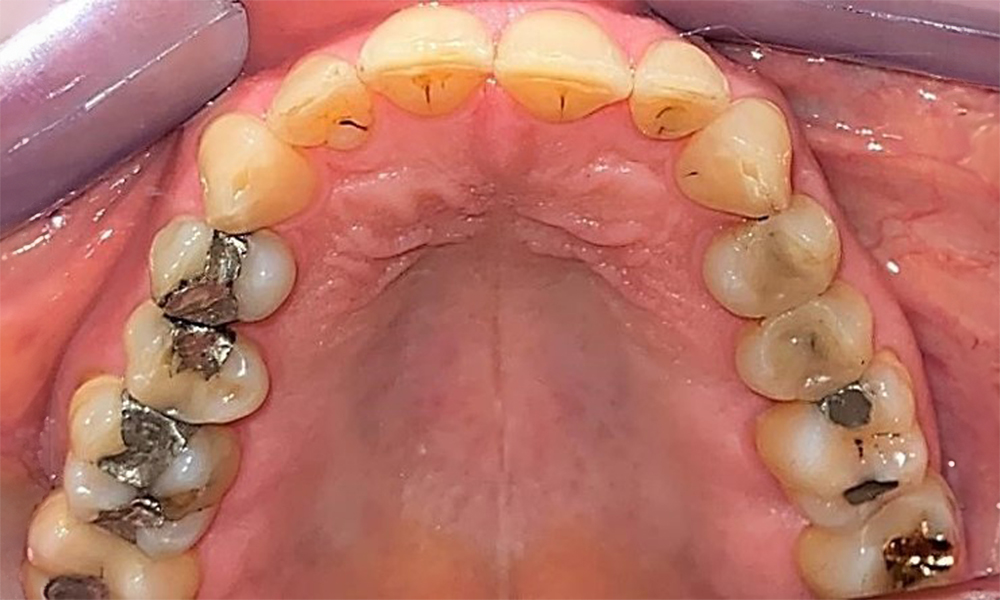

Пациентът има пълно съзъбие с 28 зъба, което включва амалгамни и композитни пломби в областта на моларите и премоларите. На зъб 14 има видима клинична маргинална празнина. Зъб 27 има адекватна златна инкрустация. Налице са и генерализирани атриции и абразии. (фиг. 2, фиг. 3, фиг. 4, фиг. 5, фиг. 6)

Пациентът е с пародонтит II стадий, степен В (5). Клиничните дълбочини на сондиране от 1 до 3 mm са във физиологичния диапазон. Локализирани дълбочини на сондиране от 5 mm са наблюдавани медиопалатинално на 17 и 27. Налице са генерализирани рецесии от 1 до 3 mm с частична загуба на интердентални папили (фиг. 2, фиг. 3, фиг. 4)